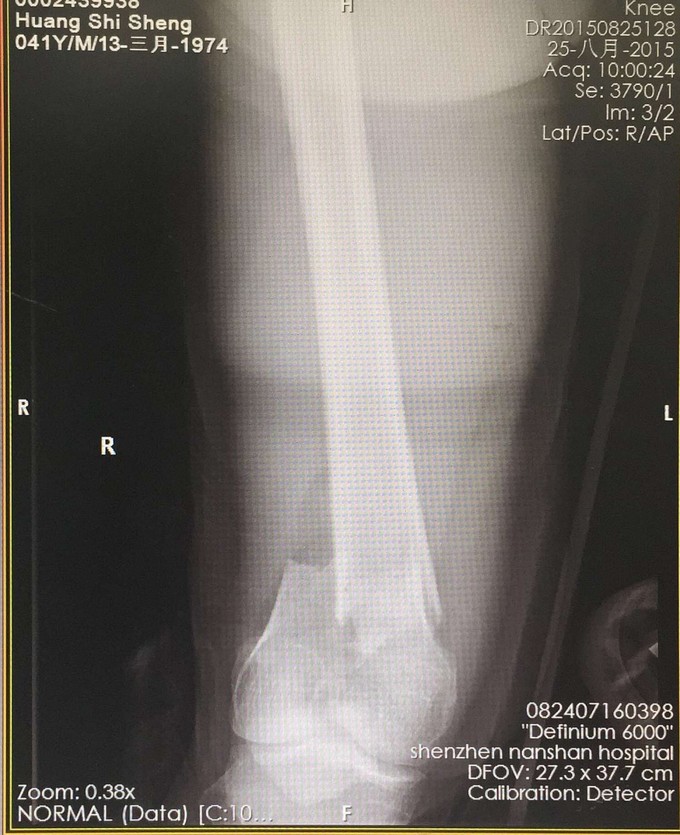

查体:右大腿中下段短缩成角畸形,肿胀,可扪及骨擦感,患肢末梢感觉血运可。 X:右股骨下端骨折 CT:右股骨下端骨折,波及关节面。

右股骨远端粉碎性骨折 完善检查,行右股骨远端骨折切开复位内固定术。